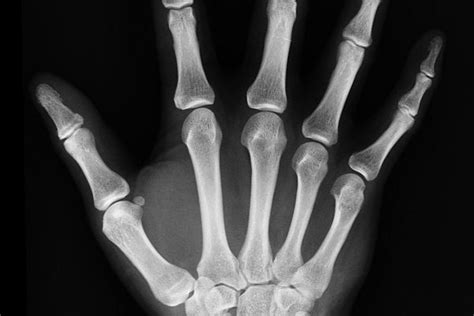

Pani Kordula pocítila okamžitú, silnú bolesť. Jej palec bol zakliesnený v medzere dverí, ktoré sa v tom čase otvorili len na pol centimetra. Sila 600 Newtonov (približne 61 kg) vyvinutá dverami spôsobila oddelenie posledného článku jej palca. Napriek šoku a vážnemu zraneniu sa jej podarilo dostať domov, kde jej manžel Heiner okamžite rozpoznal závažnosť situácie a vyhľadal lekársku pomoc. Žiaľ, ani v druhej nemocnici sa nepodarilo zranený článok palca prišiť. Dodnes Kordula Schweinebergová trpí fantómovými bolesťami a pocitmi stŕpnutosti.